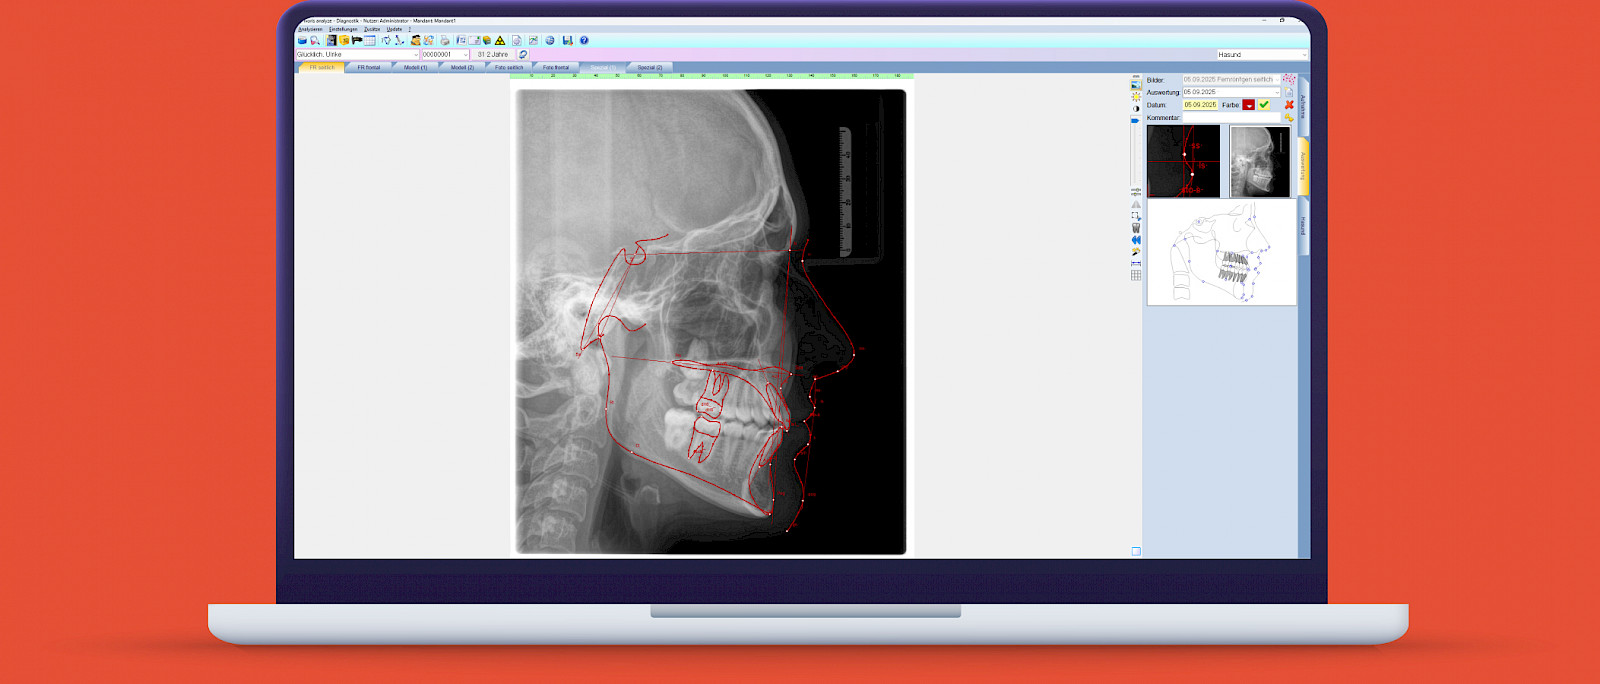

ivoris® express ceph

FRS-Analysevorschläge* in unter einer Sekunde.

Die KI in ivoris® express ceph wurde auf Basis tausender manueller Auswertungen trainiert und mit der Expertise erfahrener Kieferorthopäd:innen entwickelt. So unterstützt sie Zahnärztinnen und Zahnärzte sowie KFOs effizient bei der Befundung – mit präzisen, sofort verfügbaren Ergebnissen.

- Automatische FRS-Auswertungen in < 1 Sekunde

- KI-gestützt mit Schädel- und Weichteilstrukturen

- Präzise Unterstützung bei Befundung und Planung